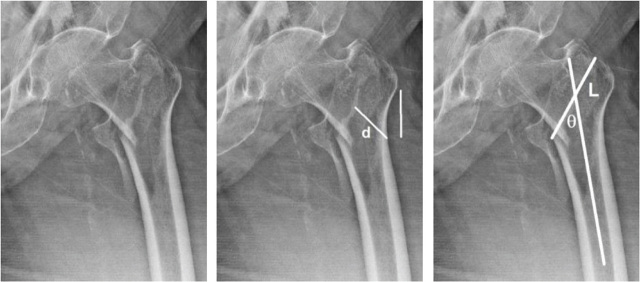

Methods: This retrospective study evaluated patients with an intertrochanteric fracture who had had surgery in King Chulalongkorn Memorial Hospital between January 2014 and January 2019. The lateral wall was measured by anteroposterior plain radiography by four raters, two times each. The demographic data and fracture parameters were assessed and compared with respect to lateral wall integrity.

Result: In a total of 236 femurs and 232 patients having the 2018 AO/OTA-specified 31A1 and 31A2 intertrochanteric fractures, the lateral wall-thickness measurement showed excellent inter-rater reliability at 0.944 (0.927-0.957) and good-to-excellent intra-rater reliability ranging from 0.835 to 0.972. The parameters associated with lateral wall incompetence as per the multivariate logistic regression analysis were fracture angle (odds ratio [OR] = 0.95), distal greater trochanter involvement (OR = 9.47), and fragments at the intertrochanter area (OR = 4.49) and at the lesser trochanter (OR = 2.6).